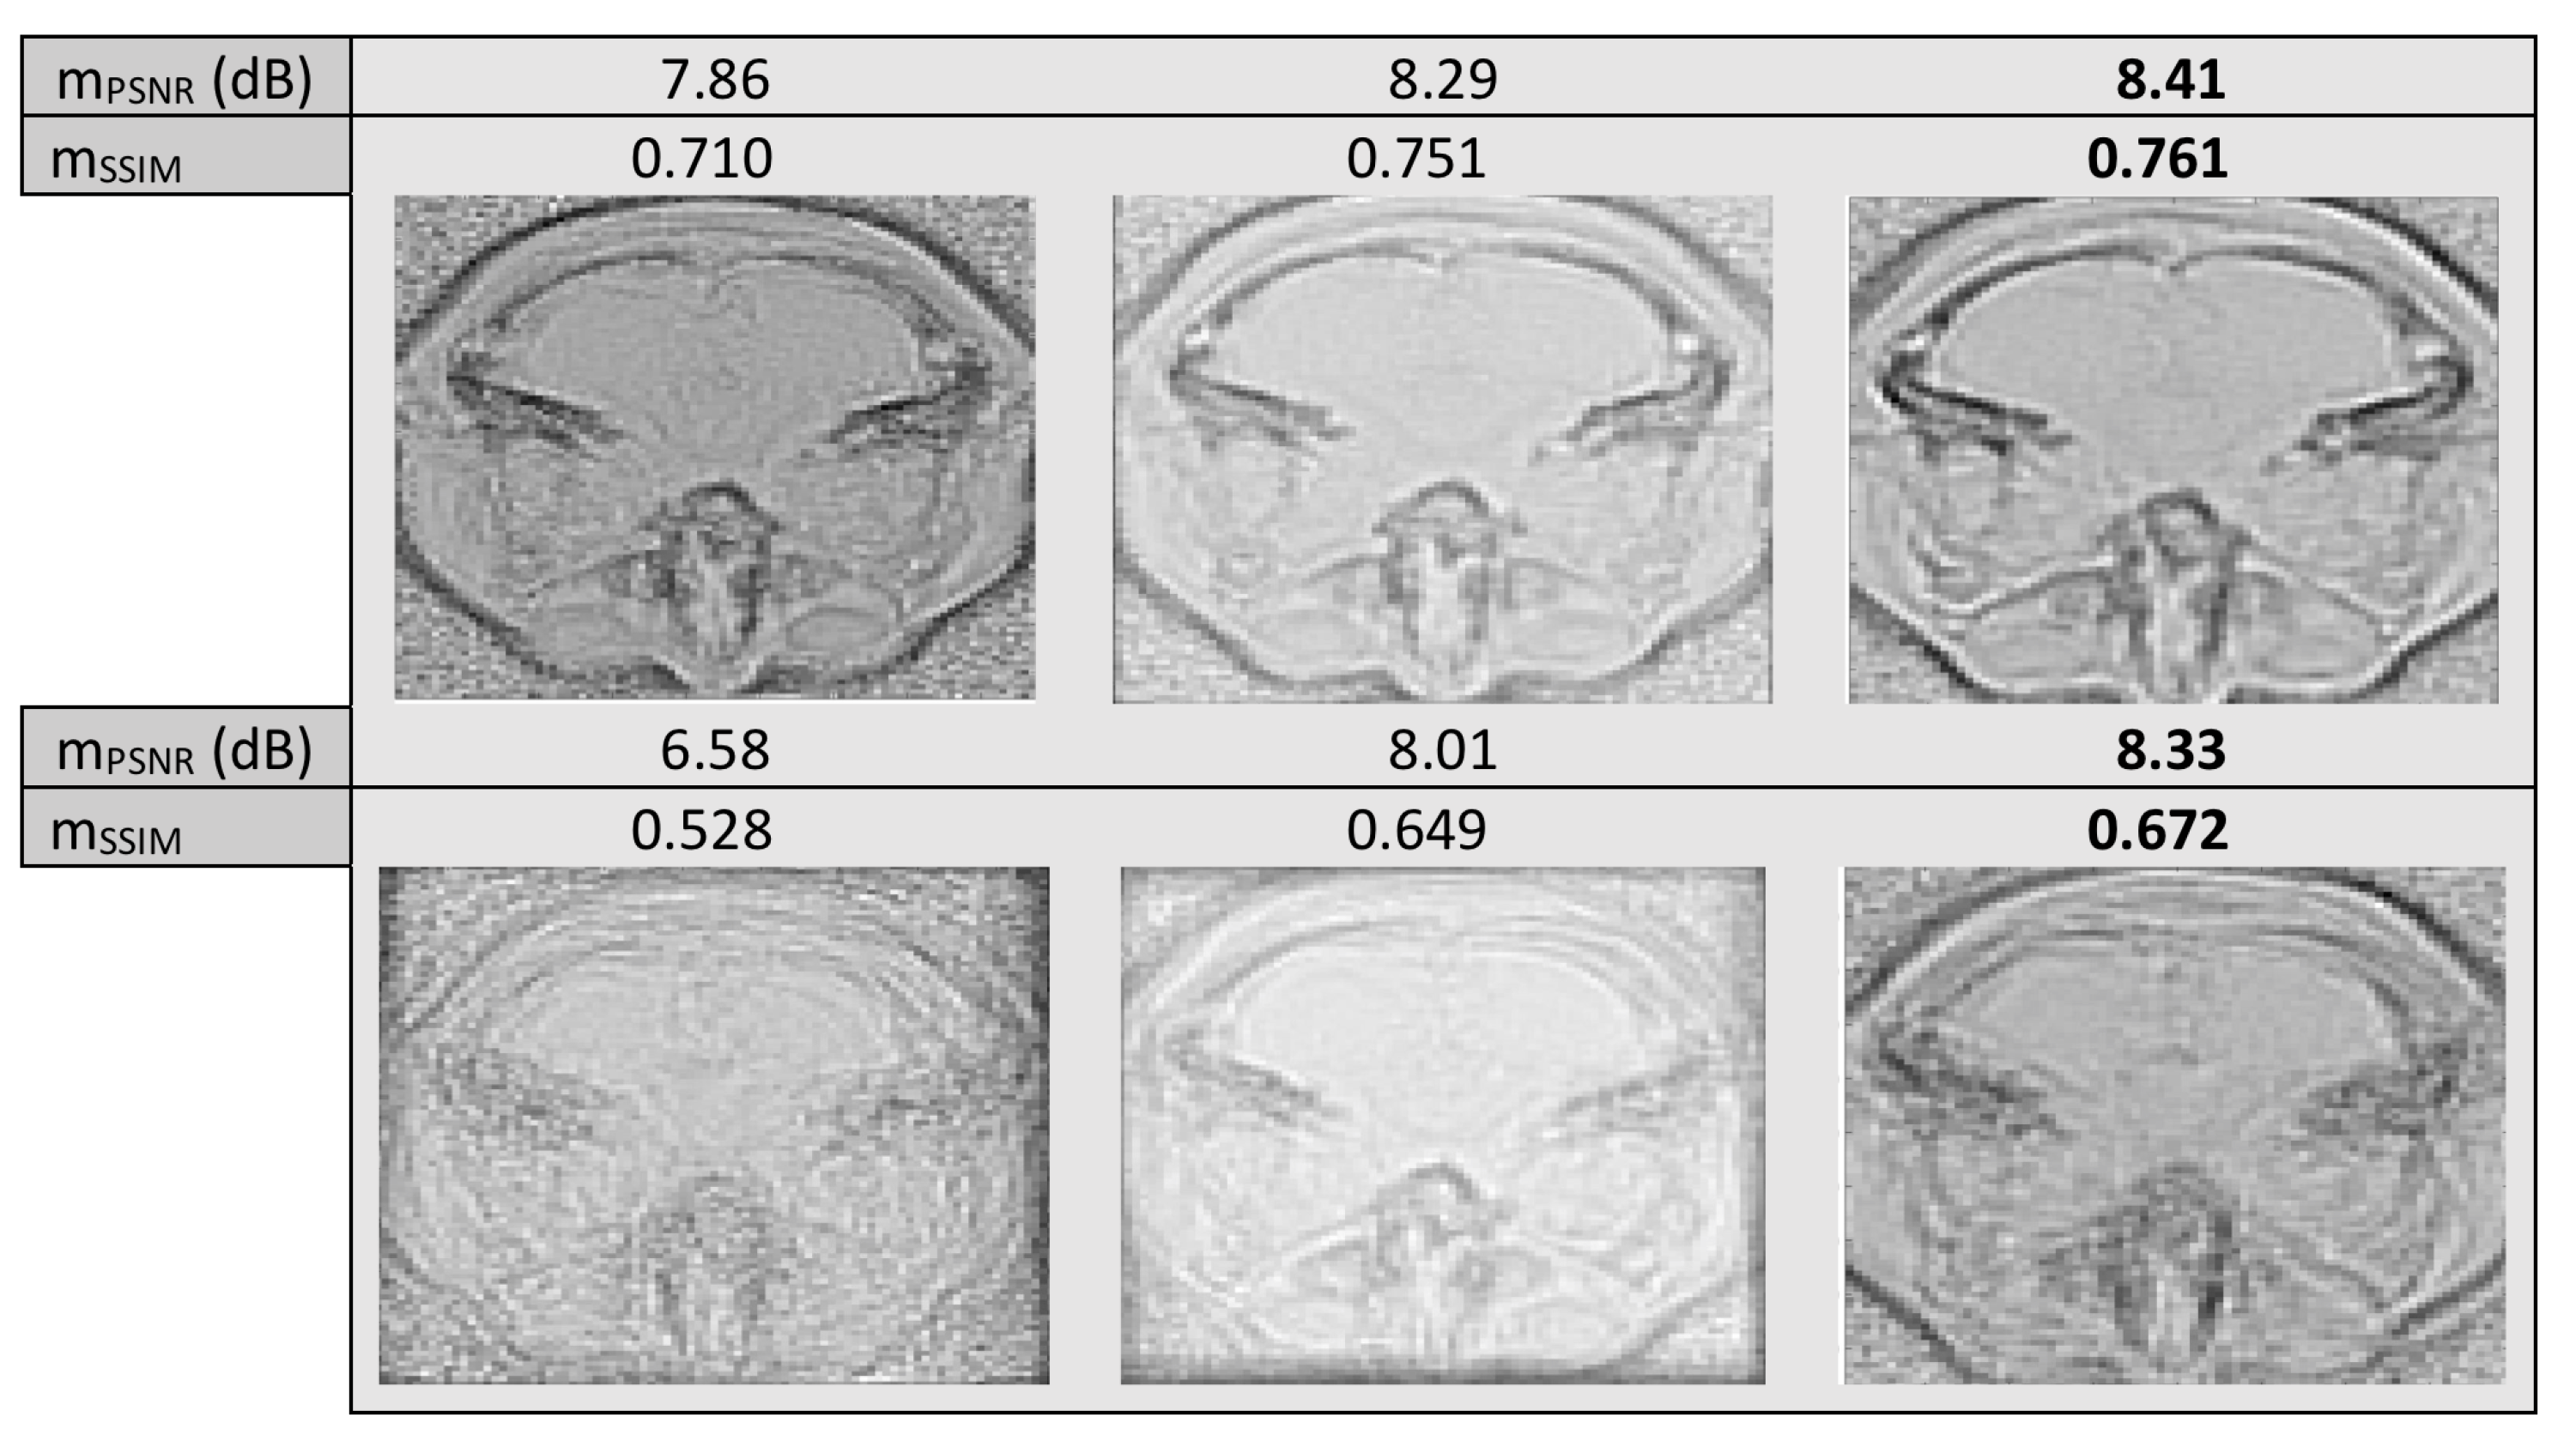

Next, we tested the methods with artificial data from the Brainweb Database, where we applied warps of to the images. We used neighboring slices of , and imaging, in a total of 35 images of size . In Figure 8 we can see the resulting “mean” image of LKE and the proposed method, as well as the original “mean” of the warped images.

Figure 8.

Mean misalignment images of , MR images with warp of (first row) and (second row). Images before alignment (first column) and after alignment with LKE (second column) and the proposed (third column).

It is evident in all three experiments conducted with MR images, unimodal or multimodal, that the mean image resulting from the proposed method has more defined edges, especially when larger warps are applied to the images, leading to a more blurred original mean, even when in some cases, in terms of , as well as , the results of the two methods, are very close. The computational cost per iteration was and s, per experiment, for the proposed and and s, per experiment, for LKE, excluding preprocessing costs. As results indicate, clearly, iteration running time depends on the size of the image set. For LKE the increase in time cost may result in large overall time cost in the case of very large sets, i.e., over 1000 images, while in the case of the proposed the increase in iteration running time is very much smaller, allowing possible testing on sets of much larger size.